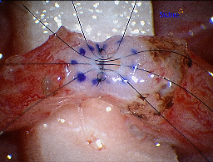

Vasectomy reversal performed by vasovasostomy is done using an operating microscope that provides magnification 25 times the normal image size. This is important since the size of the vas deferens is about the same as a piece of spaghetti and should be sewn in two-layers to offer the highest pregnancy rates. Microscopic suture (10-0 nylon) unseen by the naked eye is used during the vasectomy reversal. It is important to use this fine suture to prevent leakage of sperm and to minimize obstruction of the lumen of the vas deferens by the suture itself. The cost of the suture itself is over $900 per vasectomy reversal!

The next step in a vasectomy reversal is to re-approximate the ends of the vas deferens in a tension-free manner. The 10-0 Nylon suture provides a water-tight closure for the sperm to travel through the vas deferens. If larger sized suture is used, it can cause obstruction in the vasal lumen itself.